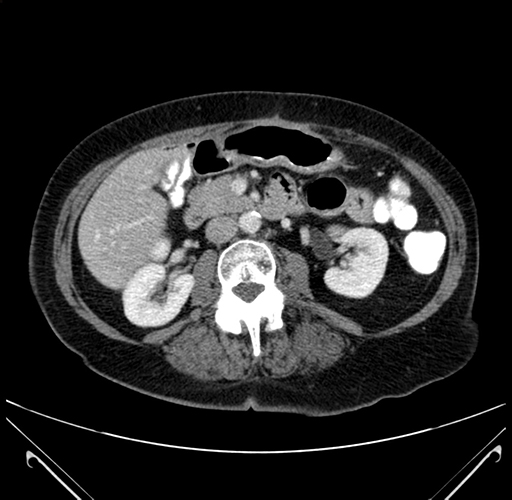

Pre-Chemo: Axial Venous

Axial Venous